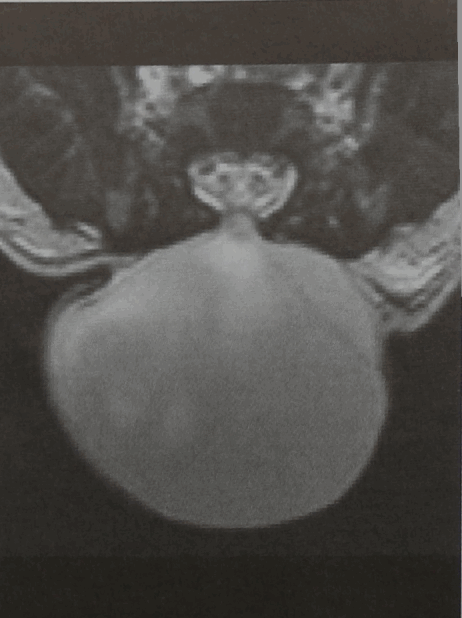

МРТ позвонка Ц/ (горизонтальная проекция, Т2-взвешенное изображение). Костный дефект закрыт соединительнотканными структурами (данные получены во время операции), через которые выпячивается грыжевой мешок, заполненный ЦСЖ. Определяется перегородка, но нервные структуры отсутствуют. Эти структуры не выходят за пределы позвоночного канала. Переднее субарахноидальное пространство не расширено. Грыжевой мешок покрыт тонким слоем кожи.